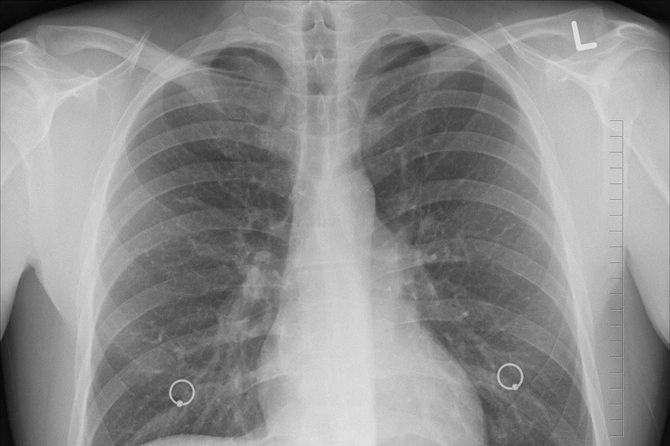

Международная группа ученых назвала причину того, почему заражение вирусами часто осложняется бактериальной пневмонией.

Известно, что наиболее частая причина смерти при тяжелом течении гриппа связана с развивающейся в виде осложнения бактериальной пневмонией.

Исследование показало, что во время вирусной инфекции питательные вещества и антиоксиданты, выделяемые организмом для борьбы с вирусом, просачиваются из крови в легкие, создавая там среду, благоприятную для роста бактерий.